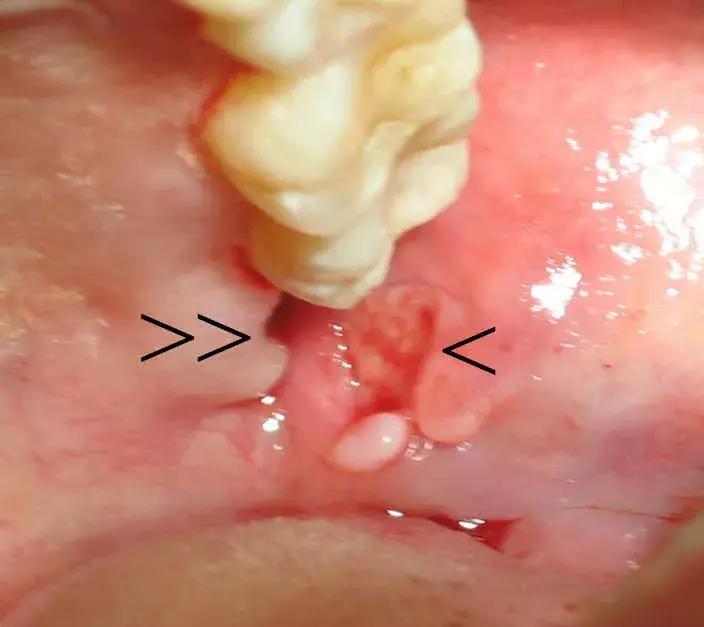

2、阻生齿拔除20天后,

牙床肿了一个包是咋回事?

图片看不太清,根据病史和上牙列情况,可能是粘液囊肿。上颌牙齿反复咬破下牙床引起的。

5、这种情况咋回事?要拔吗?

智齿下面的牙齿是下颌双尖牙异位了,位置很深,需要定期密切视察。和智齿一起拔的话,骨折风险不低。即便拔,建议拍个CBCT,住院拔。